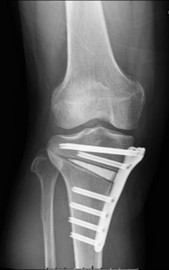

変形性膝関節症、膝関節骨軟骨障害

加齢性変化による疾患では変形性膝関節症が多く、単顆型を含めた人工膝関節置換術はもちろん、適応があれば骨を温存することのできる膝周囲(大腿骨遠位・高位脛骨)骨切り術も行っています。若年者の軟骨損傷に対しては損傷の程度に応じて骨軟骨柱移植術・骨軟骨片固定術・培養軟骨移植術を行っています。

高位脛骨骨切り術